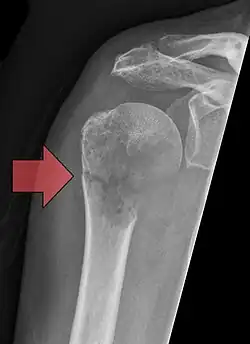

| Pathological fracture of the humerus in a patient with metastasis of renal cell carcinoma | |

A pathologic fracture is a bone fracture caused by weakness of the bone structure that leads to decrease mechanical resistance to normal mechanical loads.[1] This process is most commonly due to osteoporosis, but may also be due to other pathologies such as cancer, infection (such as osteomyelitis), inherited bone disorders, or a bone cyst. Only a small number of conditions are commonly responsible for pathological fractures, including osteoporosis, osteomalacia, Paget's disease, Osteitis, osteogenesis imperfecta, benign bone tumours and cysts, secondary malignant bone tumours and primary malignant bone tumours.

Pathological fractures present as a chalkstick fracture in long bones, and appear as a transverse fractures nearly 90 degrees to the long axis of the bone. In a pathological compression fracture of a spinal vertebra fractures will commonly appear to collapse the entire body of vertebra.